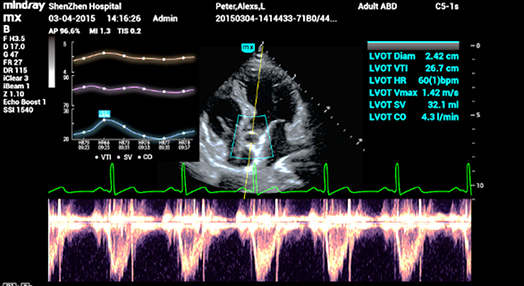

2Smart VTI

Automatic measurement of the VTI (Velocity Time Integral) and CO (Cardiac Output), for rapid assessment of cardiac function. Automatically locate color box and PW sample line on real time. A graph of parameters trends about CO, SV and VTI to guide the decision-making.